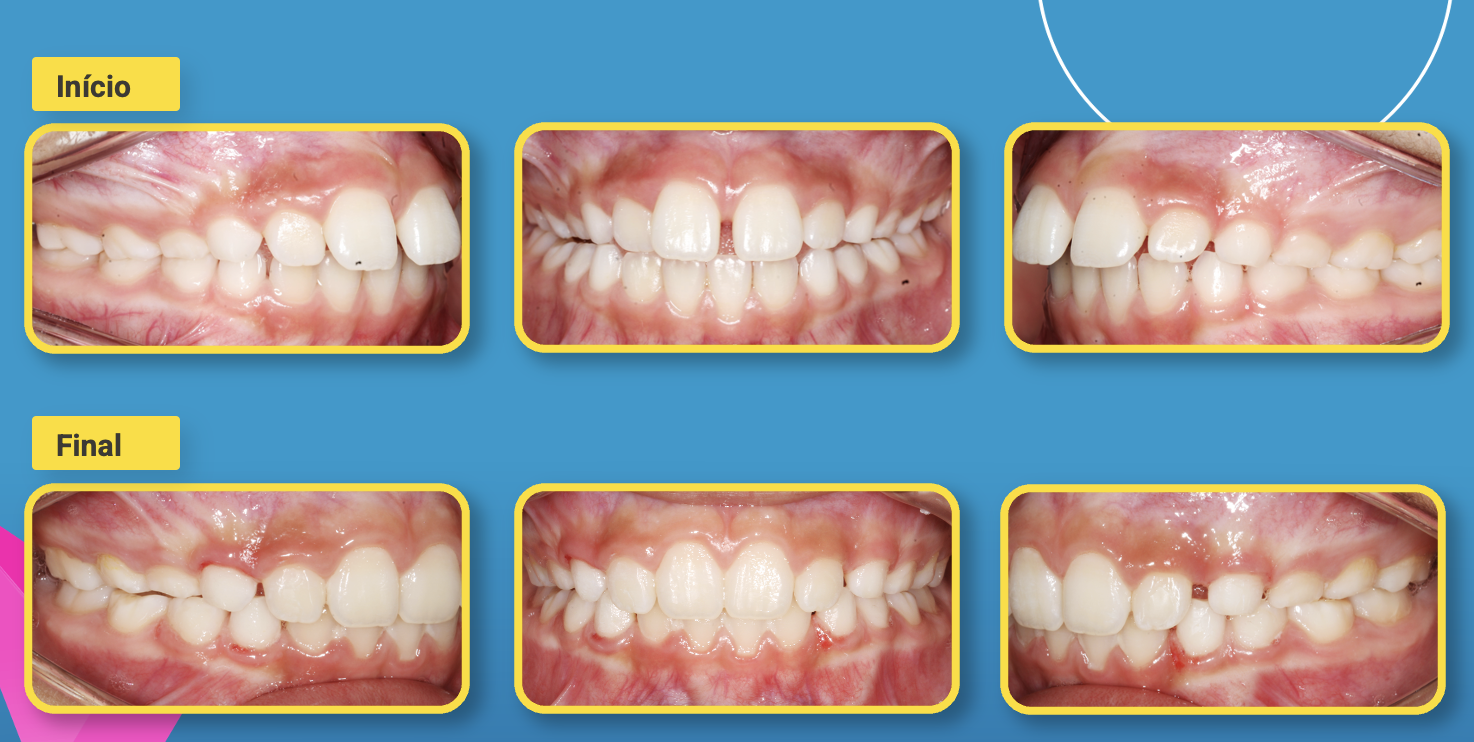

Invisalign First – Ortodontia Infantil com Conforto e Precisão

O Invisalign First é o sistema de alinhadores transparentes desenvolvido especialmente para crianças em fase de crescimento. Ele corrige problemas de mordida e alinhamento de forma confortável, removível e praticamente invisível, tornando o tratamento muito mais fácil para os pequenos e para os pais.

8. O tratamento é eficaz mesmo em crianças pequenas?

Sim. Diversos estudos e casos clínicos mostram que o Invisalign First é eficaz e previsível quando bem indicado e acompanhado por um ortodontista experiente.

9. Quanto tempo dura o tratamento?

O tempo varia conforme o caso e os objetivos do tratamento, mas em média dura entre 12 e 18 meses na fase inicial. Posteriormente, o ortodontista pode indicar outras fases de acompanhamento até a adolescência.